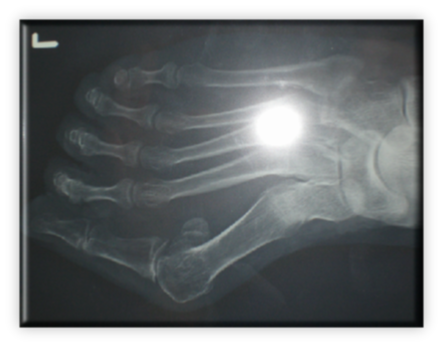

ΒΛΑΙΣΟΣ ΜΕΓΑΛΟΣ ΔΑΚΤΥΛΟΣ (HALLUX VALGUS)

Στις ακτινογραφίες πρέπει να μετρηθούν η γωνία μεταξύ 1ου και 2ου μεταταρσίων με ανώτερα όρια 8-9 μοίρες, η γωνία βλαισσότητας του 1ου μεταταρσίου και 1ης φάλαγγας που όταν ξεπερνά τις 15 μοίρες ορίζεται παθολογική. Συμπληρωματικά μπορούν να μετρηθούν οι γωνίες προσανατολισμού της αρθρικής επιφάνειας κεφαλής 1ου μεταταρσίου και η γωνία προσανατολισμού κεντρικής αρθρικής επιφάνειας 1ης φάλαγγας του μεγάλου δακτύλου.

Τονίζεται ότι στην κλινική εξέταση υποχρεωτικά ελέγχεται όλο το κάτω σκέλος από το γόνατο και κάτω, όλες οι επιφάνειες του άκρου ποδός σε στήριξη και όχι, το εύρος κίνησης των αρθρώσεων οπισθίου, μέσου και περιφερικού άκρου ποδός, η αναταξιμότητα των παραμορφώσεων, μήκος μεταταρσίων, νευροαγγειακός έλεγχος.

Αρχικά, η αντιμετώπιση είναι συντηρητική με αντιφλεγμονώδη επιθέματα, περιποίηση δέρματος, κινησιοθεραπεία αρθρώσεων, χρήση κατάλληλων υποδημέτων και ειδικών ναρθήκων ανάταξης.

Ο κατάλληλος χρόνος χειρουργικής αντιμετώπισης είναι εξειδικευμένος για κάθε περιστατικό, λαμβάνοντας υπόψη την ύπαρξη όλων των ανωτέρω παραμέτρων και την επίδραση που έχουν στη λειτουργικότητα αλλά και αισθητική του άκρου ποδός. Γενικότερα η επέμβαση δεν είναι απαραίτητο να γίνεται υπερβολικά νωρίς απλά και μόνο επειδή κάποιες γωνίες στις ακτινογραφίες είναι πάνω από το φυσιολογικό, αλλά ούτε και υπερβολικά καθυστερημένα  καθιστώντας το χειρουργείο πραγματική πρόκληση από τεχνική άποψη. Περιγράφονται περί τα 150 είδη επεμβάσεων για τη συγκεκριμένη παθολογία και τις παραλλαγές της. Είναι έργο του χειρουργού σε πλήρη συνεργασία με τον ασθενή να επιλεγεί η κατάλληλη επέμβαση για τον κατάλληλο ασθενή στον κατάλληλο χρόνο. Περιγράφονται επεμβάσεις από τις πιο απλές, συνθετότερες με τεχνικές ελάχιστης επεμβατικότητας έως και πολύ σύνθετες.